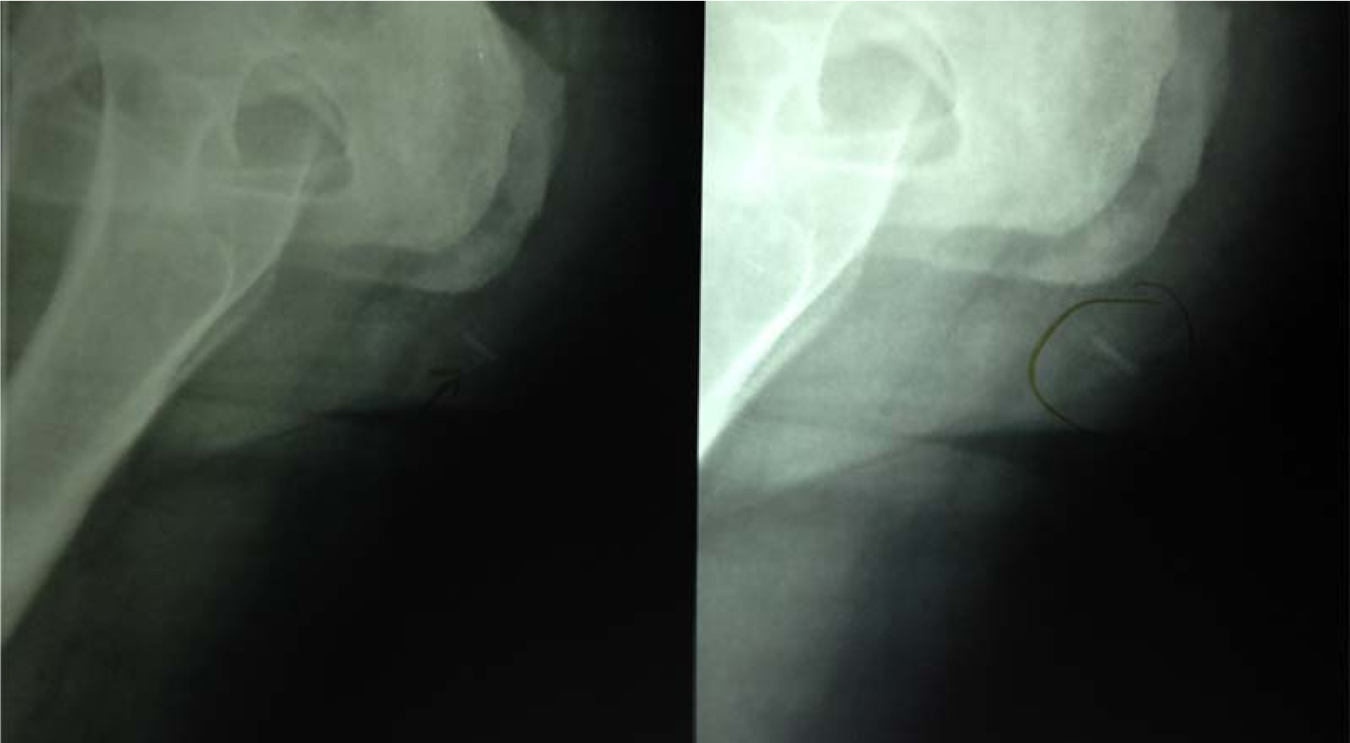

Ecchymosis

Differential Etiologic Diagnosis : Husband or Ex Boy Friend Behaviour